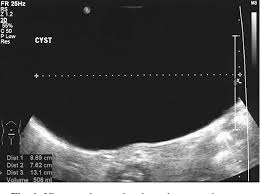

Both ovariesdemonstrate a normal sonographic appearance. Beyond this, any pouch or sac filled with fluid or other tissue that formed on the ovary is also an ovarian cyst. 3 may 2019 21:52 in response to mumoftwo34. The right ovary measures 2.5 x 2.2 x 1.7 cm and contains a 2.2 cm simple cyst. Symptoms of ovarian torsion include nausea, vomiting, and pain in the lower belly or pelvis. Is a 3.4 cm ovarian cyst big? These grow to about 2.5 cm, or one inch, and then when the woman ovulates or releases the egg the cyst drains and is gone. Ovarian cancer and cysts have similar symptoms and signs, for example, pain during intercourse, pelvic pain, and urinary problems. Using a laparoscope — a slim, lighted instrument inserted into your abdomen through a small incision — your doctor can see your ovaries and remove the ovarian cyst. In the month of june 08, both my ovaries were normal without any sign of cyst. Ovaries are actively making hormones and ripening eggs from when the period first starts until when she goes through menopause. Complex ovarian cysts are very rare but they can cause many serious problems and complications, including emotional isolation because of the condition. Ovulation happens when these cysts are around 2 to 3 cm in size.

The left ovary measures 2.1 x 2.0 x 1.5 cm. Most functional cysts are 2 to 5 centimeters (cm) (about 3/4 of an inch to 2 inches) in size. But if the ultrasound shows that the cyst is still growing then it requires a more serious approach. Is a 3.4 cm ovarian cyst big? I was diagnosed as having a 9.1 cm ovarian cyst in my right ovary two days ago.

Complex cysts are more likely to need treatment than simple cysts. He said according to the report, there no urgency, meaning. A normal ovary is about 2 x 3 cm (almond sized). It is estimated that 5% of all abdominal masses in the first month of life are ovarian cysts. A follicular ovarian cyst, if the egg is not ejected and the amount of fluid continues to increase, can reach sizes of up to 10 cm.